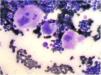

Bone marrow aspiration revealed increased cellularity, the relative hyperplasia of the erythroid precursors with dysplastic changes, myeloid precursors with normal maturation, and an increase in the number of megakaryocytes. Platelet detachment was not seen (Figure 1).